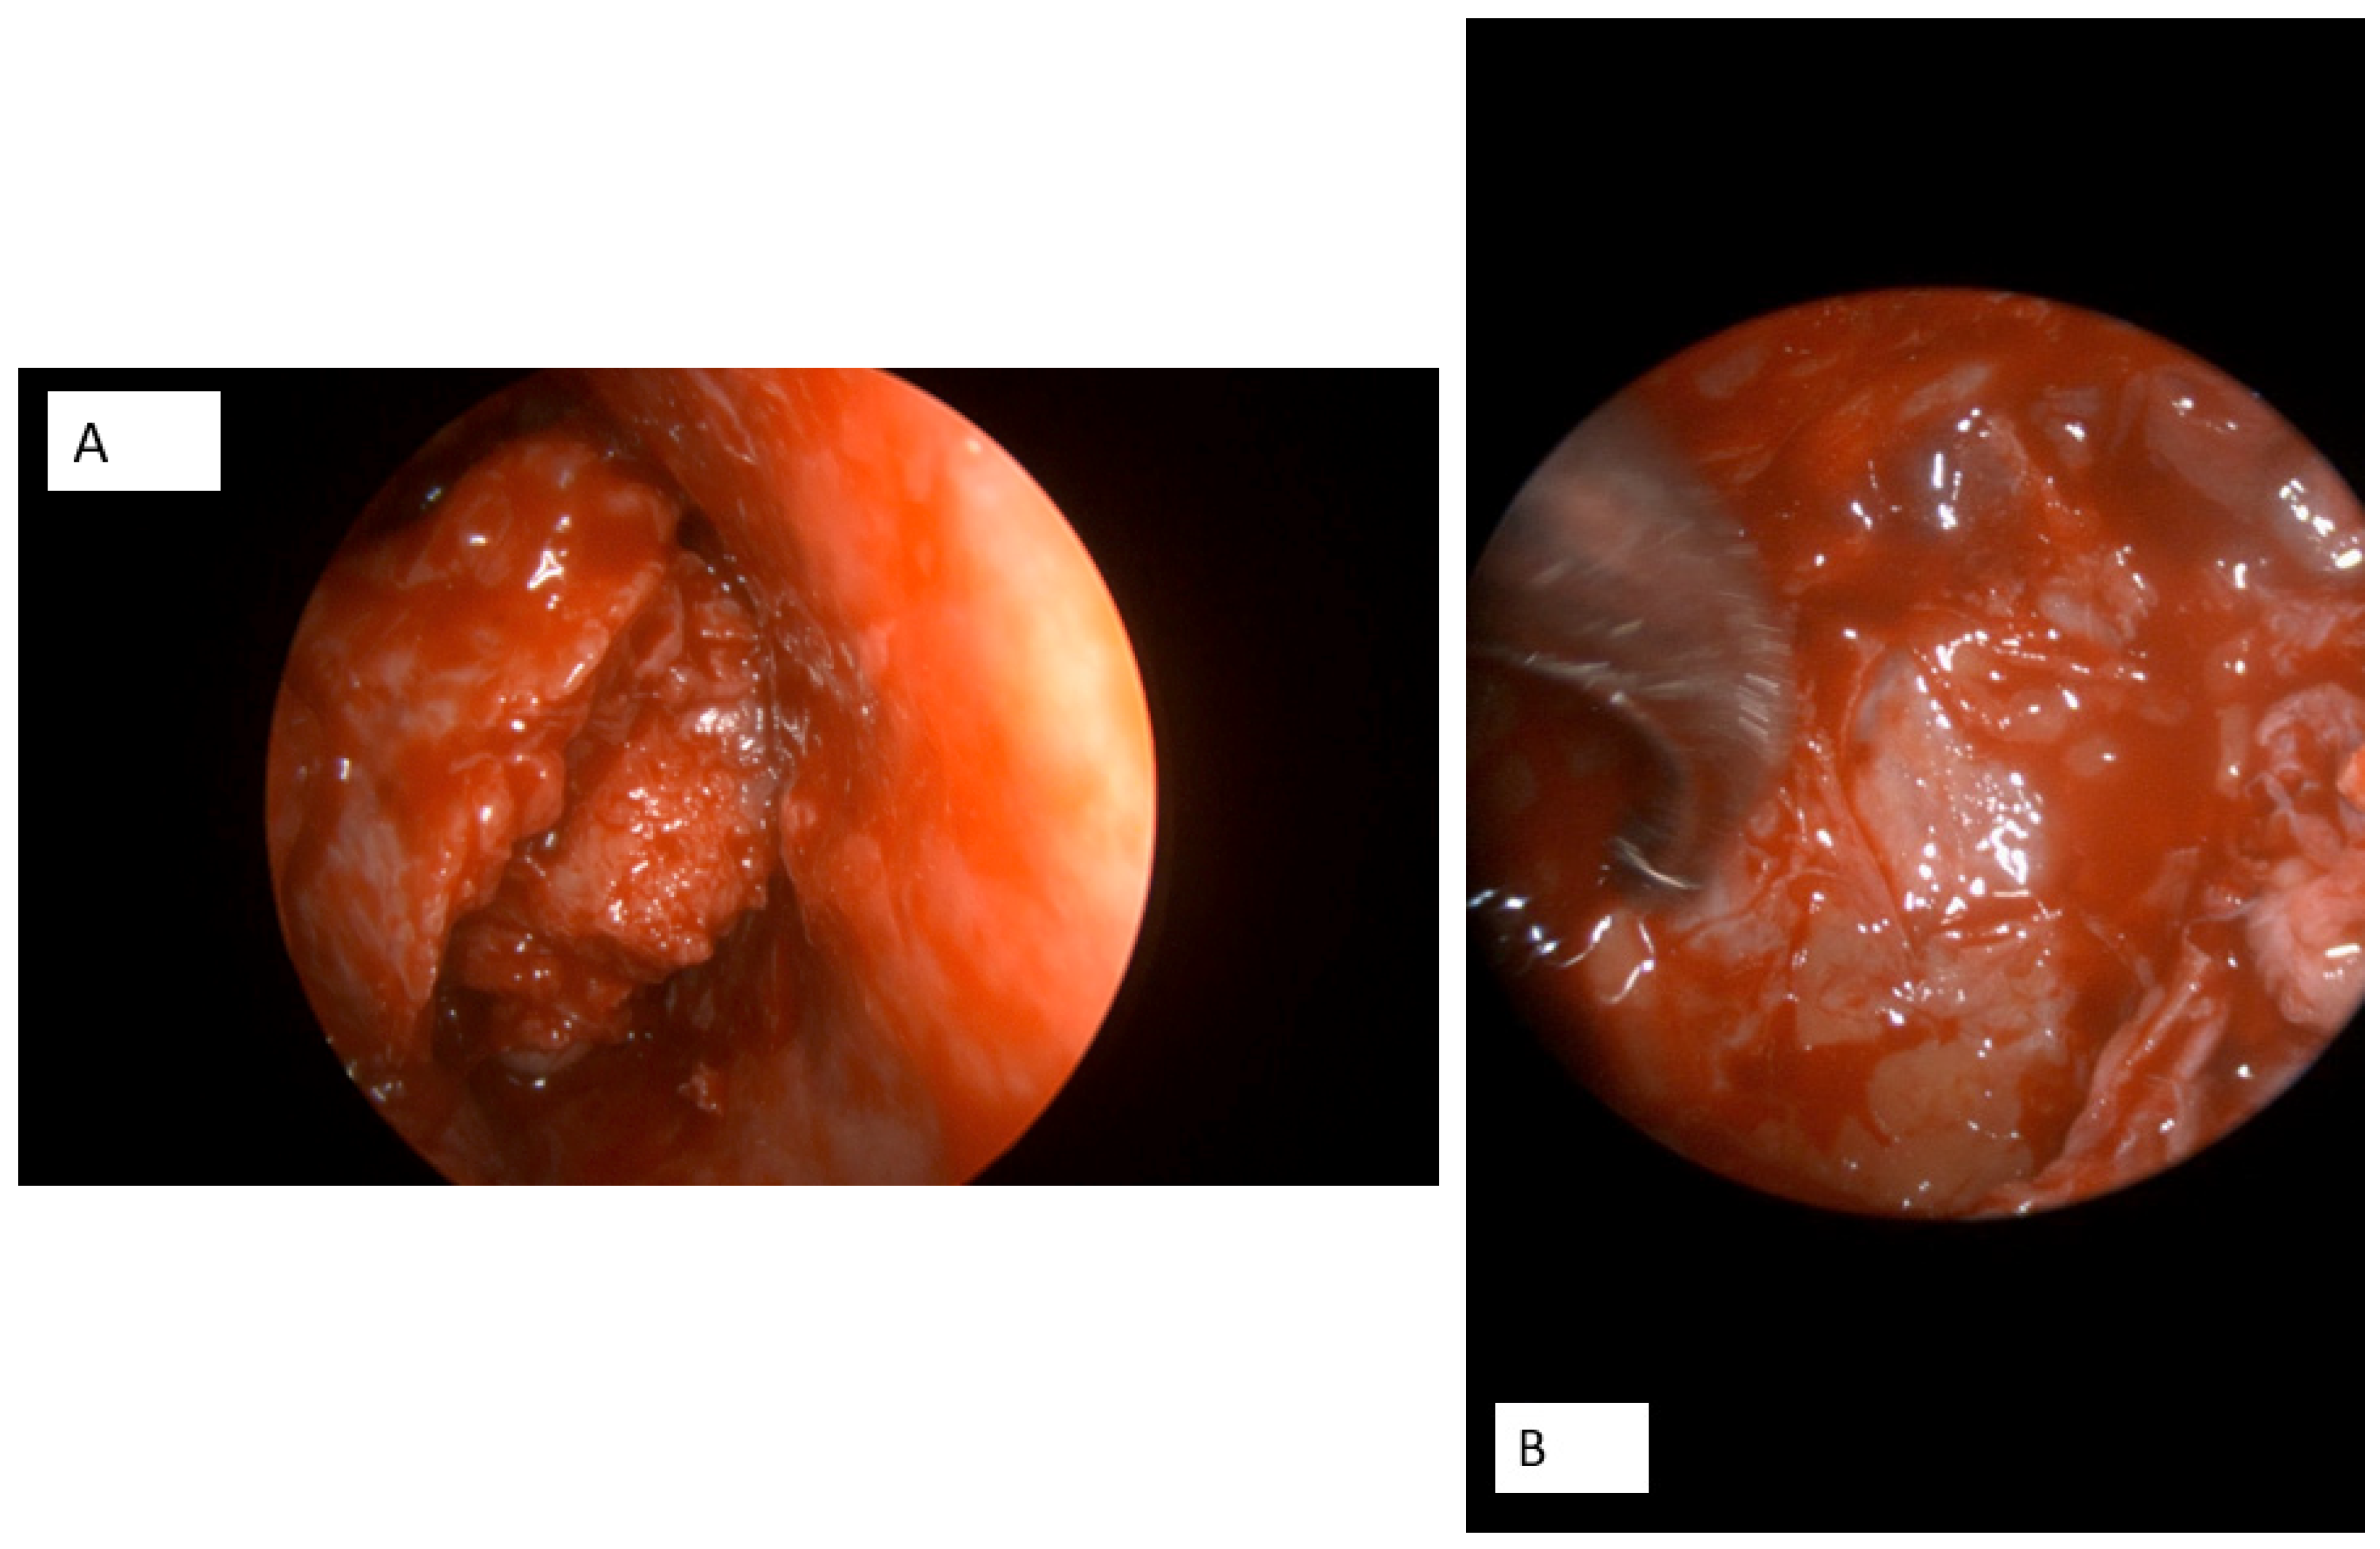

2. Case Presentation